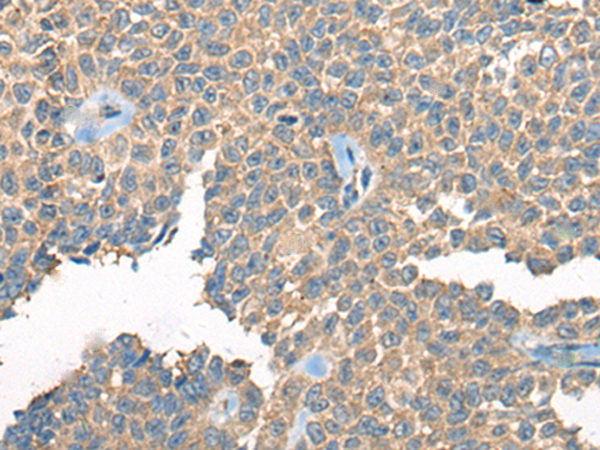

分类: 科研抗体货号: P09430别名: CAMKKA应用: WB,IHC反应种属: Human, Mouse, Rat